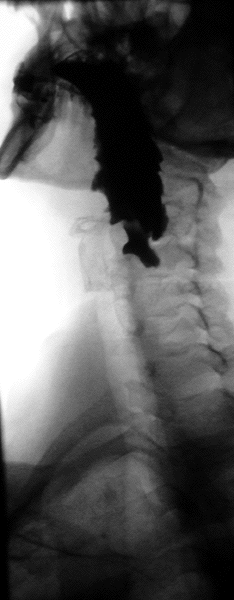

Radiologen teilen die Zenker-Divertikel nach Brombart in vier Stadien zunehmender Schwere ein:

- Stadium 1 ist eine dornenförmige, 2–3 mm lange Nischenbildung, die auch nicht immer sichtbar wird.

- Divertikel im Stadium 2 sind 7–8 mm groß und keulenförmig.

- Divertikel im Stadium 3 sind über 10 mm groß, sackförmig und nach unten umgebogen.

- Im Stadium 4 komprimiert das Divertikel die Speiseröhre und behindert sichtbar dessen Kontrastmittelpassage.[3]

Die Diagnostik erfolgt bei entsprechenden Symptomen mit der Endoskopie und Röntgenaufnahmen mit Kontrastmittel. Sobald ein Patient Schluckstörungen bemerkt, sollte er sich in fachärztliche Betreuung begeben, denn diverse Erkrankungen der Speiseröhre können diese Beschwerden hervorrufen. Danach sollte eine genaue Inspektion von Mund und Rachen des Patienten erfolgen und der Hals nach vergrößerten Lymphknoten oder Weichteilveränderungen abgetastet werden. Je nach Verdachtsdiagnose wird eine Spiegelung der Speiseröhre durchgeführt und gleichzeitig im Bereich auffälliger Schleimhautbereiche eine Gewebeprobe entnommen. Ergänzend, vor allem bei Divertikeln, wird eine Röntgenuntersuchung der Speiseröhre mit flüssigem Kontrastmittel durchgeführt, die auch Bewegungsstörungen der Speiseröhrenwand zeigen kann. Handelt es sich bei der Erkrankung um einen Tumor, ist es unter Umständen notwendig, eine zusätzliche CT- oder MRI-Untersuchung durchzuführen, um seine Ausdehnung und Lage im Brustkorb zu sehen. Unter Umständen ist auch eine Voruntersuchung durch einen Hals-Nasen-Ohren-Arzt notwendig, der die Funktionsfähigkeit eines wichtigen Nervs im Bereich des Kehlkopfes überprüfen muss. Je nach Vorerkrankungen und Alter des Patienten werden auch Ultraschalluntersuchungen am Herzen sowie eine Lungenfunktionsprüfung durchgeführt. Bei einem Zenker-Divertikel ist die Indikation zur Operation gegeben, völlig unabhängig davon, wie stark die Beschwerden des Patienten sind, denn die Komplikationsrate ist gering.